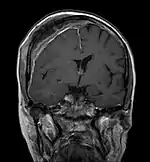

Imagerie par résonance magnétique

Avec l'IRM, on peut en particulier obtenir de bonnes images des tissus mous. C'est un processus idéal pour le diagnostic des métastases spinales (métastases des vertèbres). Avec l'IRM, on peut en outre rendre visible des complications supplémentaires dans la région des métastases spinales, comme des infections ou des blessures des tendons et ligaments, des œdèmes de la moelle osseuse après une fracture récente[120],[121], ou la compression de structures nerveuses[18]p. 16. Au moyen de séquences STIR, il est possible d'évaluer l'âge d'une fracture. Pour la détection des métastases, la pondération T1 avec des produits de contraste au gadolinium, comme l'acide gadotérique est particulièrement bien adaptée. Le produit de contraste s'accumule particulièrement fort dans les métastases[18],[122].

Pour le diagnostic des récidives (2), l'IRM est plus adapté que le scanner. Par exemple, les implants de titane font moins d'artefacts pour l’IRM[87],[123].

- Comparaison scanner/IRM pour des métastases ostéolytique d'un cancer du sein dans la colonne vertébrale

IRM natif avec pondération T1.

IRM sagittal natif avec pondération T1. On voit clairement l’extension jusqu'aux lames vertébrales.